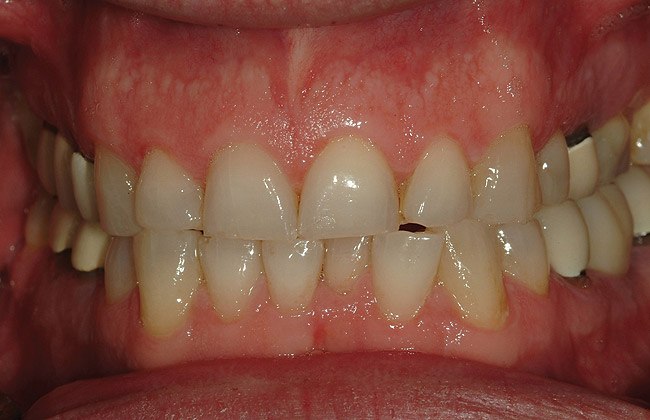

Figure 6  Preoperative retracted view of the dentition.

Figure 6